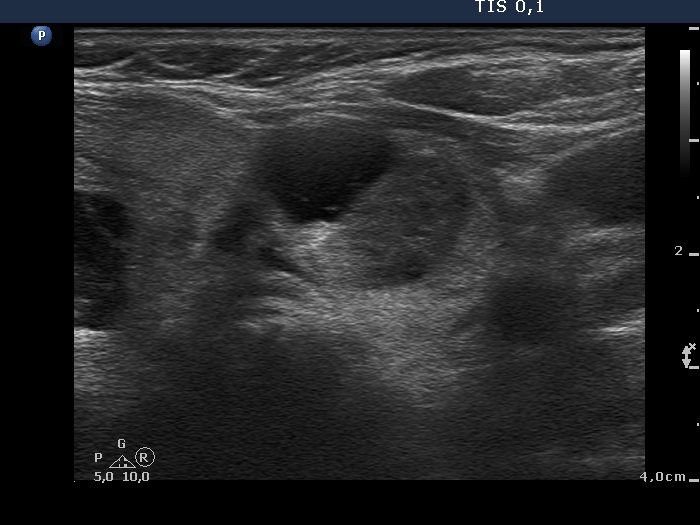

Study on 100 consecutive patients with thyroid nodule - case 061 (ultrasonographic picture 7)

Isthmic part of the left lobe, transverse scan. There is a moderately hypoechogenic nodule presenting cystic degeneration.